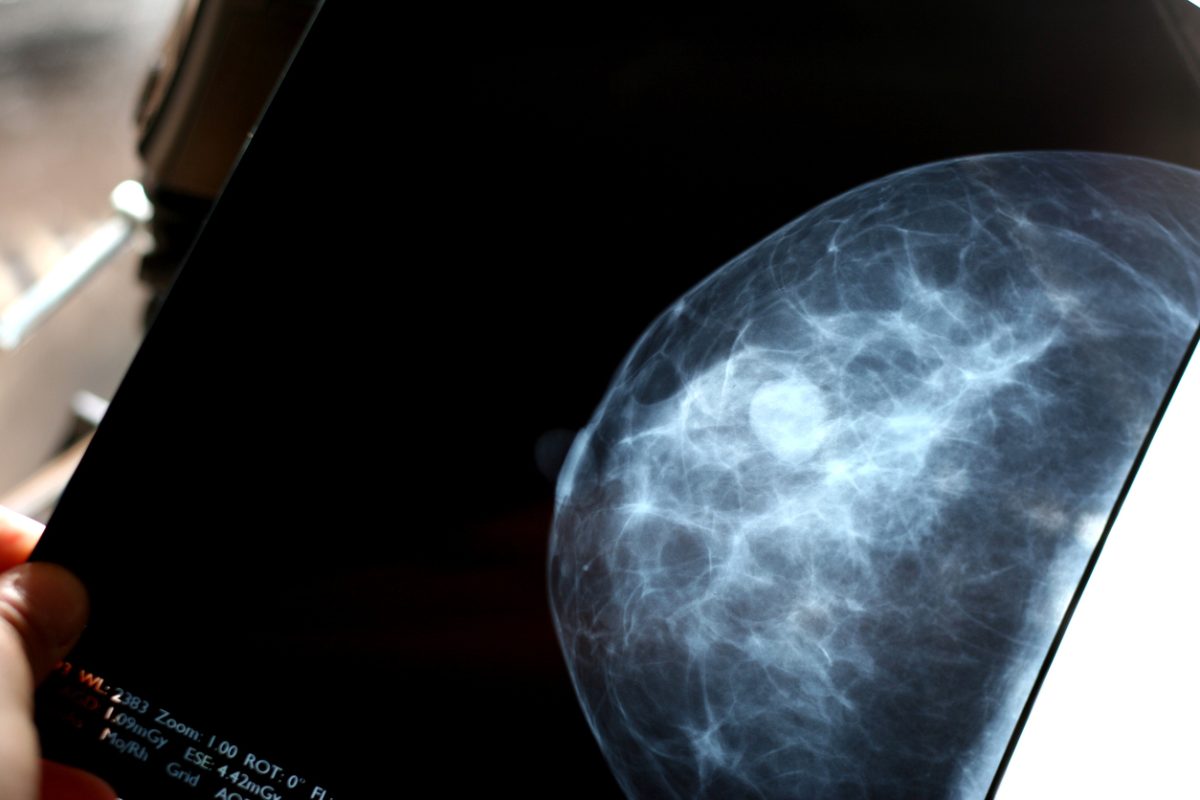

Non vengono ancora utilizzate nella pratica clinica, ma probabilmente lo saranno in un futuro non troppo lontano. Sulla base della conoscenza di queste varianti genetiche si potrebbe mettere a punto un test per stimare un “indice di rischio poligenico” specifico per ciascuna donna. E in base a questo indice, e agli altri fattori di rischio conosciuti, si potrebbero eseguire screening di prevenzione nella popolazione. Oggi, per esempio, si valuta che il migliore rapporto tra rischi e benefici per la popolazione femminile in termini di prevenzione del tumore al seno si ha cercando di individuare eventuali lesioni con la mammografia a partire dai 45-50 anni. In futuro si potrebbe essere in grado di fare una sorveglianza anticipata o più stretta indirizzata alle donne che hanno un rischio genetico che si è dimostrato più alto.